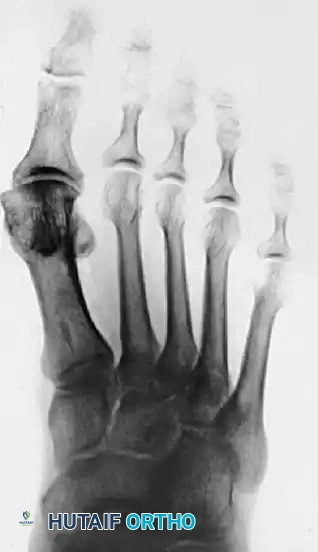

Figure 1: Anteroposterior radiograph of the right foot of a 65-year-old patient showing mild-to-moderate deformity and mild degenerative changes at the first MTP joint; the patient presented with both intra-articular and periarticular symptoms.